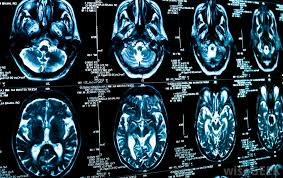

Getting scanned as an outpatient, either at a hospital or imaging center after having scheduled it. Ct scans take different amount of times depending on which part of the body is being scanned. How long does a ct scan take? The beam takes a spiral path during the scanning, so it gathers continuous data with no gaps between images. Do you get a cat scan when you have a concussion?

Find out how you have it and what happens it takes pictures from different angles. In an emergency, like a stroke alert, where a possible stroke is brought by ambulance to the er, the team of neuro nurses and neurologists will. Ct (or cat) stands for computed. Ask your doctor or nurse how long it will take to get them. Do they not understand that this is torture? Ct scan without contrast (head, sinus, orbits, abdomen, pelvis, cervical, thoracic, lumbar and dental scans) take approximately 15 minutes. How does a ct or cat scan work? If i saw a patient in the er after hours and needed a ct i would go to the control room and watch the. A ct scan can take anywhere from 15 minutes to an hour to complete. But they can also cause cancer. Your scan results won't usually be available immediately. The test will take about 30 to 60 minutes. A computer will need to process the the amount of radiation you're exposed to during a ct scan varies, depending on how much of your body is scanned.

Do you get a cat scan when you have a concussion? Ask your doctor or nurse how long it will take to get them. Since they affect the screening results, metal objects such as. A computer will need to process the the amount of radiation you're exposed to during a ct scan varies, depending on how much of your body is scanned. Ct scans are sometimes referred to as cat scans or computed tomography scans. How long does it take to get cat scan results back? Your radiologists will review and interpret your ct scan as soon as it's completed. The average ct scan of the head takes. Why does ct require a prep, and cat scan does not.?answer this question. A ct scan can take anywhere from 10 to 30. If you had medication for anxiety, pain, you should have someone how: It doesn't take long for a doctor to review a ct scan and interpret the results. A radiologist, a physician who specializes in reading and interpreting ct scan and other radiologic images, will review your scan and prepare a report that explains them.